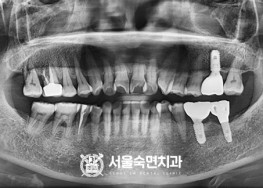

임플란트-치료-전후사진